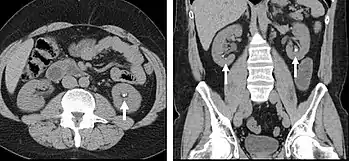

The most common technique is to perform portal venous phase imaging in the abdomen and pelvis (approximately 60-90 seconds after contrast administration, figure 2). This results in near optimal contrast opacification of the majority of the solid abdominal organs and it is used for a wide variety of indications: nonspecific abdominal pain; hernia; infection; masses (with a few exceptions such as hypervascular, renal, and some hepatic tumors); and in most follow-up examinations. As a general rule, this single phase is adequate unless there is a specific clinical indication that has been shown to benefit from other phases.

FIGURE 2. Contrast enhanced CT demonstrating parenchymal enhancement of the intra-abdominal organs in the portal venous phase (axial left, coronal reformat right).